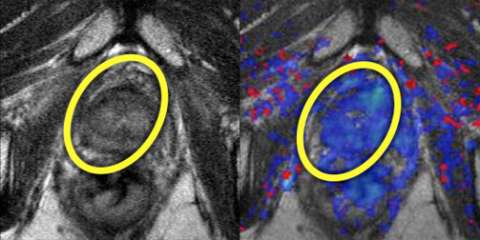

LEFT: T2-weighted image prior to treatment shows large, low-signal mass (yellow oval) on the right crossing midline anteriorly

RIGHT: Color perfusion map shows correspondingly decreased perfusion (blue pixels) consistent with response to treatment.